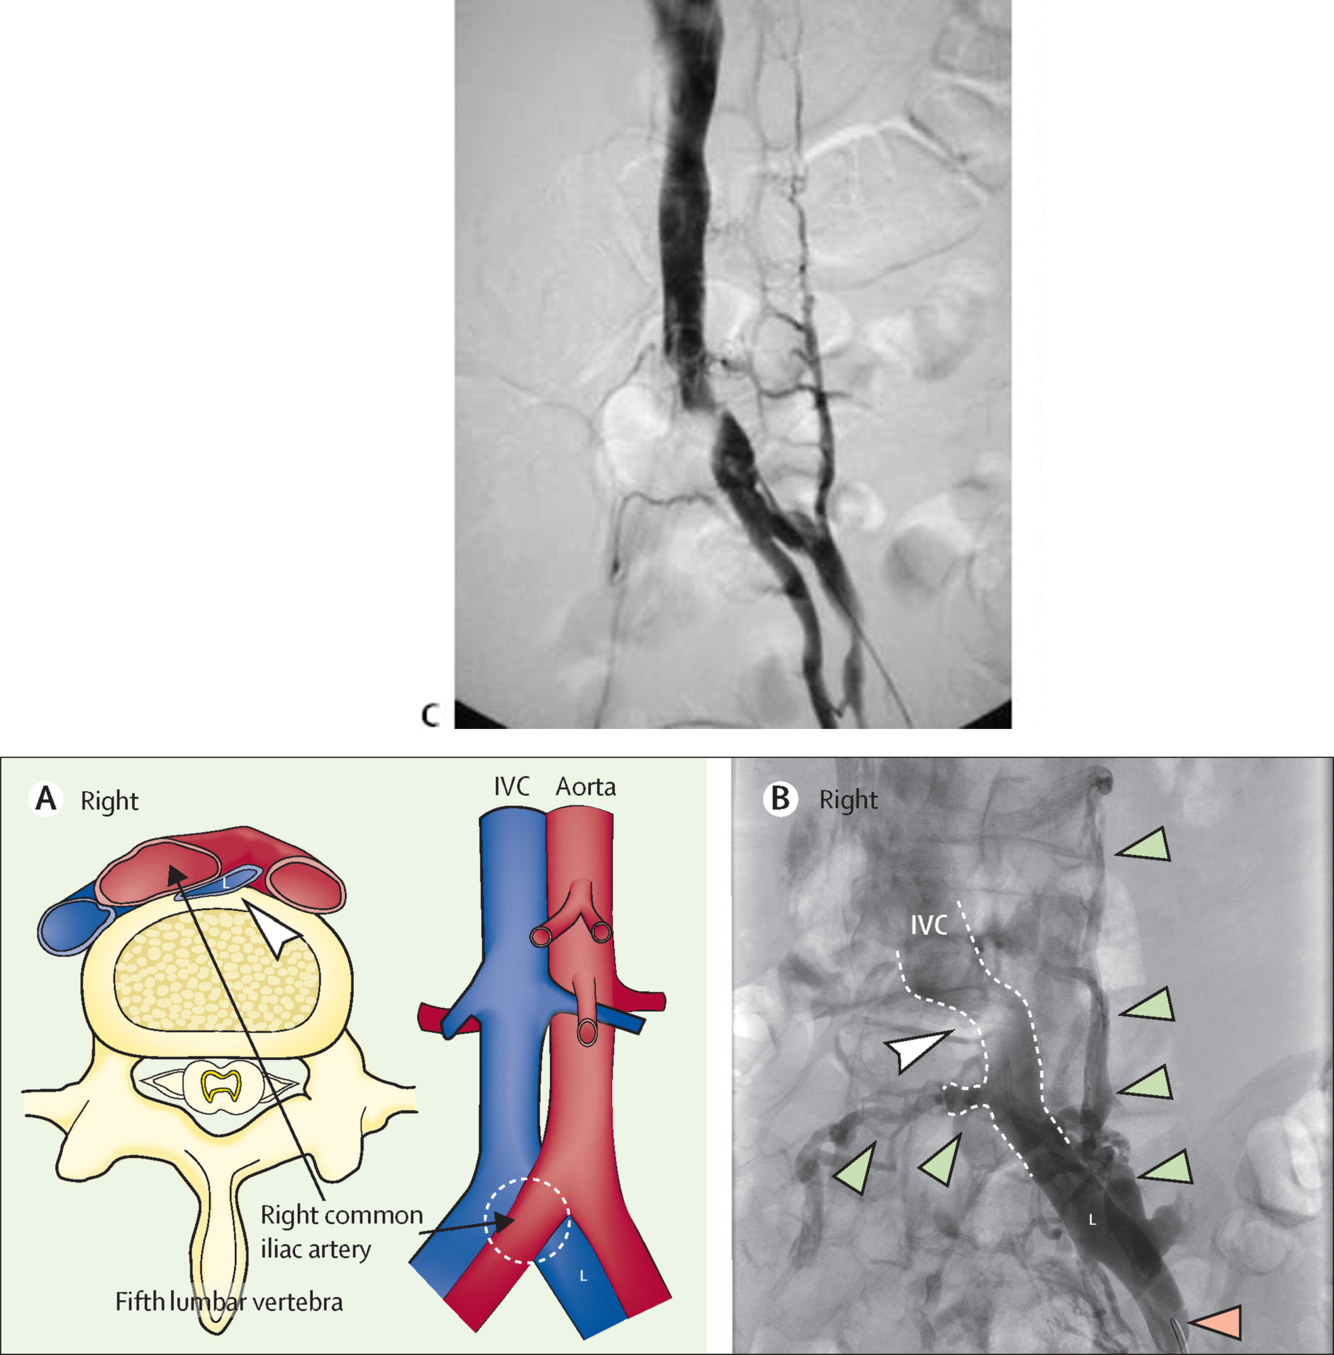

duplicated IVC

Empties into left renal vein

Can place two filters in each IVC or place a suprarenal filter

megacava

28 mm